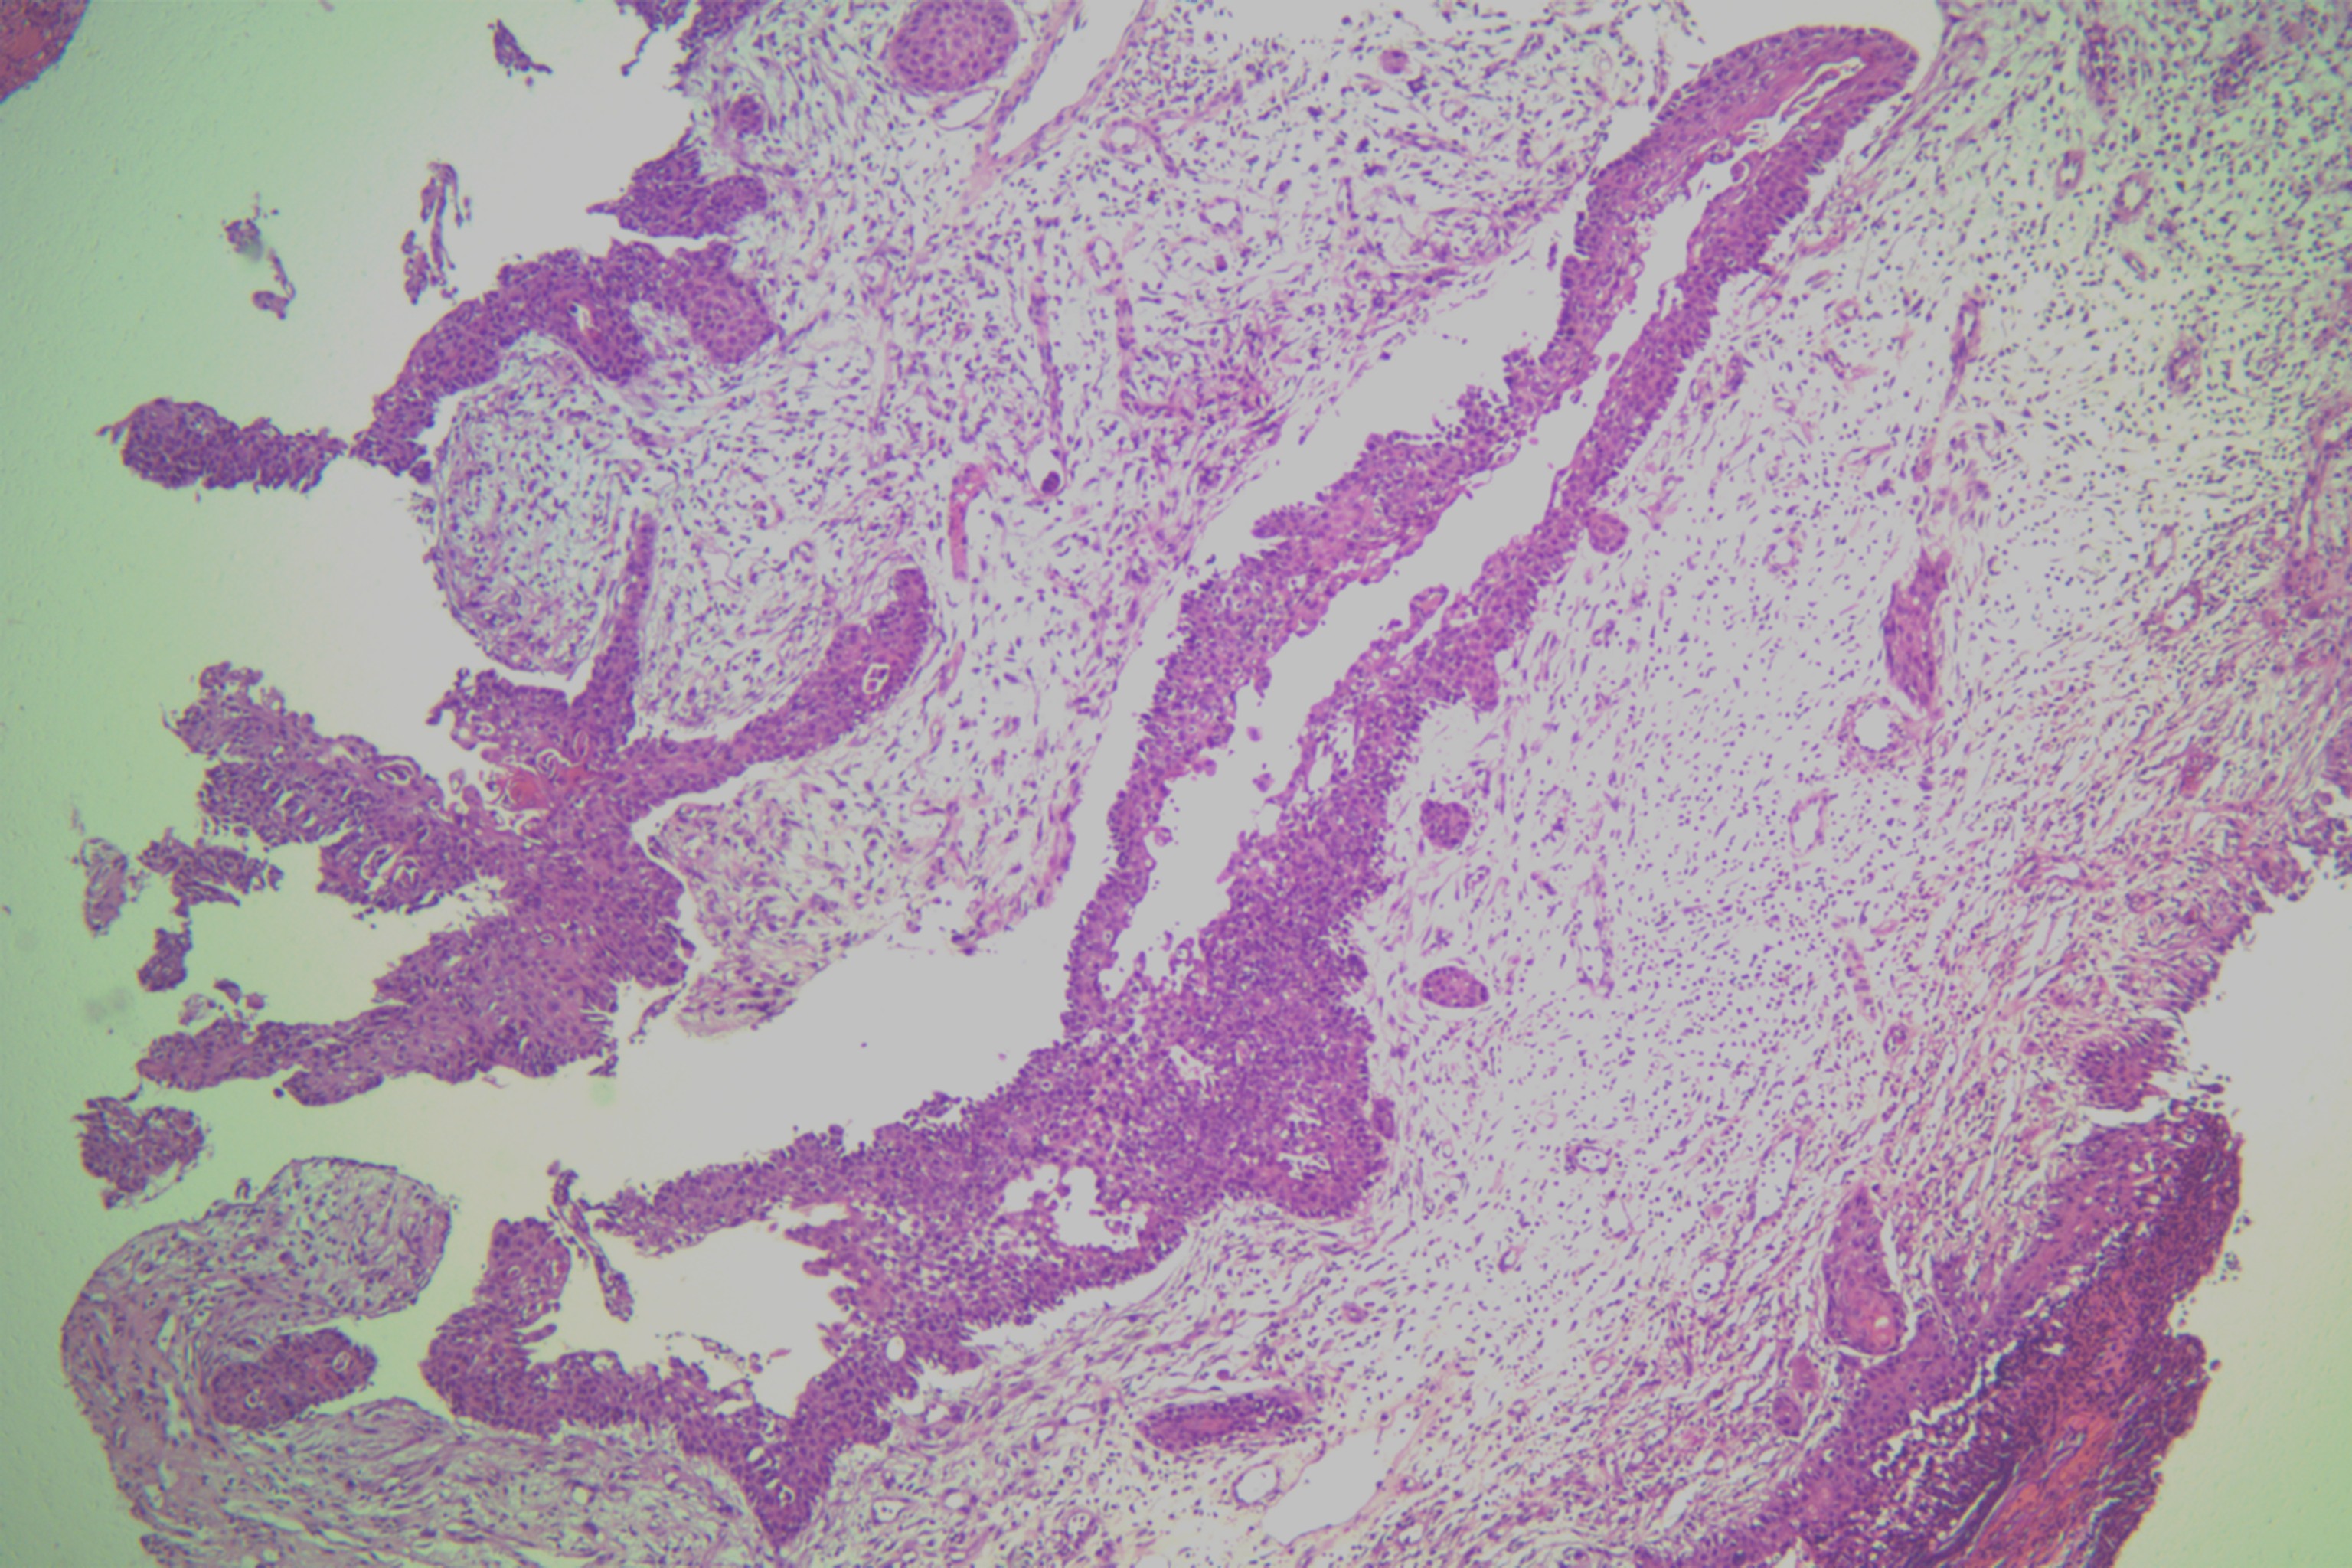

鳞癌?

性别

男

年龄

68岁

头皮肿物20年,包块逐渐增大,反复破溃

头皮肿物(局部活检)

1.5*1*0.3cm灰红碎组织一堆

考虑:基底细胞癌